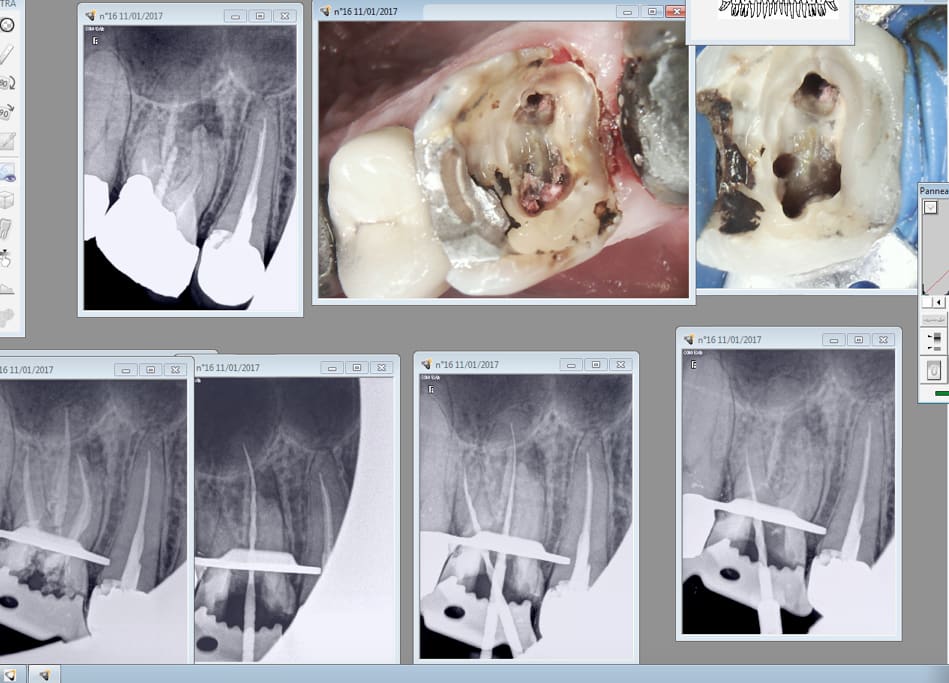

Reciproc blue.

A l'air moins agressif que le normal mais d'une efficacité incroyable. Pas de récapitulation pour aller à l'apex.

Capture d écran 2017 01 11 12.59 - Eugenol